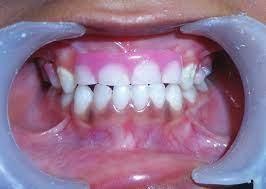

Y văn xác nhận trẻ có tuổi nhỏ hơn khoảng 14 -16 tuổi thì hàm giữ khoảng sẽ là giải pháp tốt nhất, khoảng trống sẽ đảm bảo răng không bị nghiêng đổ chờ cho đến khi các bé đủ tuổi trồng implant.

Hàm giữ khoảng là khí cụ bằng nhựa hoặc kim loại, có thể tháo lắp hoặc cố định vào cung răng nhằm mục đích giữa cho khoảng cần thiết khi răng mất hoặc không có răng tại vị trí đó. Hàm giữ khoảng là một thiết bị chờ, khi mà trẻ còn bé chưa trồng được răng thì thiết bị chờ đảm bảo sự phát triển bình thường của cả xương hàm và khớp cắn.